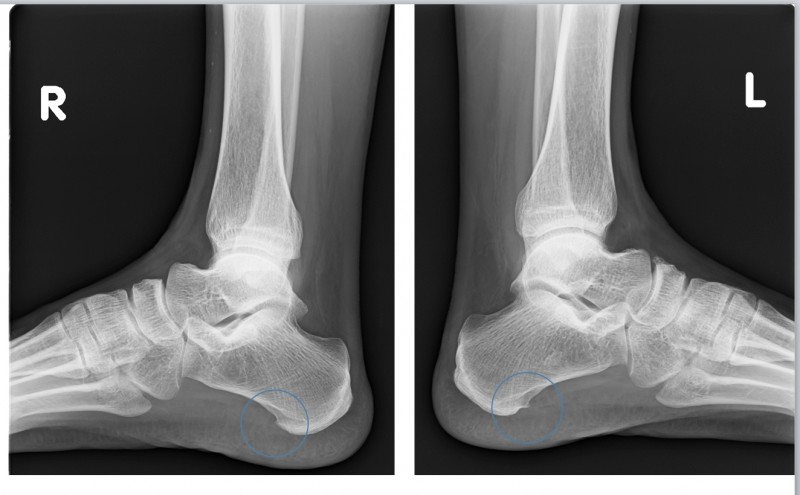

진단 방법: 육안으로도 확인 가능, X-ray로 변형 정도 측정

부산무지외반증 은 엄지발가락이 바깥쪽으로 휘어지면서 발 안쪽에 돌출부가 생기는 질환으로, 심한 경우 관절염으로 진행될 수 있으며 특히 여성에게 많이 발생합니다.

유전적 요인도 있지만, 좁고 앞이 뾰족한 신발을 오랫동안 신거나 발에 맞지 않는 신발 착용이 주요 원인입니다.

아침에 통증이 심해지는 이유는 수면 중 발의 자세가 변화하면서 변형된 관절에 압력이 가해지기 때문입니다.

또한 밤새 약간의 부종이 생긴 상태에서 아침에 갑자기 체중을 실으면 변형된 관절 부위에 통증이 더욱 심해집니다.

진단 방법: X-ray나 CT로 추가적인 뼈 확인, 발의 내측 돌출과 압통

부산부주상골증후군 은 발의 안쪽 아치 부분에 위치하는 작은 추가 뼈로, 사람에 따라 뼈가 있기도 하고 없기도 합니다.

이 뼈가 있는 경우 주변 인대나 건에 염증을 일으켜 증후군이 발생할 수 있습니다.

아침에 통증이 심한 이유는 밤새 휴식 상태였던 발이 갑자기 체중을 받으면서 부주상골 주변 조직에 압력이 가해지기 때문입니다.

특히 발의 안쪽 아치 부분에서 통증을 느끼게 됩니다.